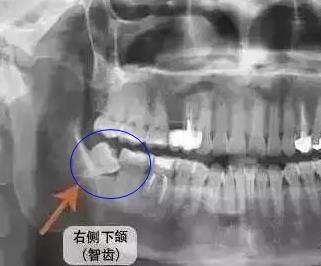

當然,特殊情況除外。如果是智齒本身智齒,則有影響。位置不正的智齒蛀牙通常不需要補牙,隻需要拔除智齒即可;還有如果是智齒頂著前麵的磨牙了,而且造成磨牙齲壞了,這時候可能需要先拔除智齒後才能對磨牙進行補牙或者是拔除了。

智齒造成鄰牙齲壞